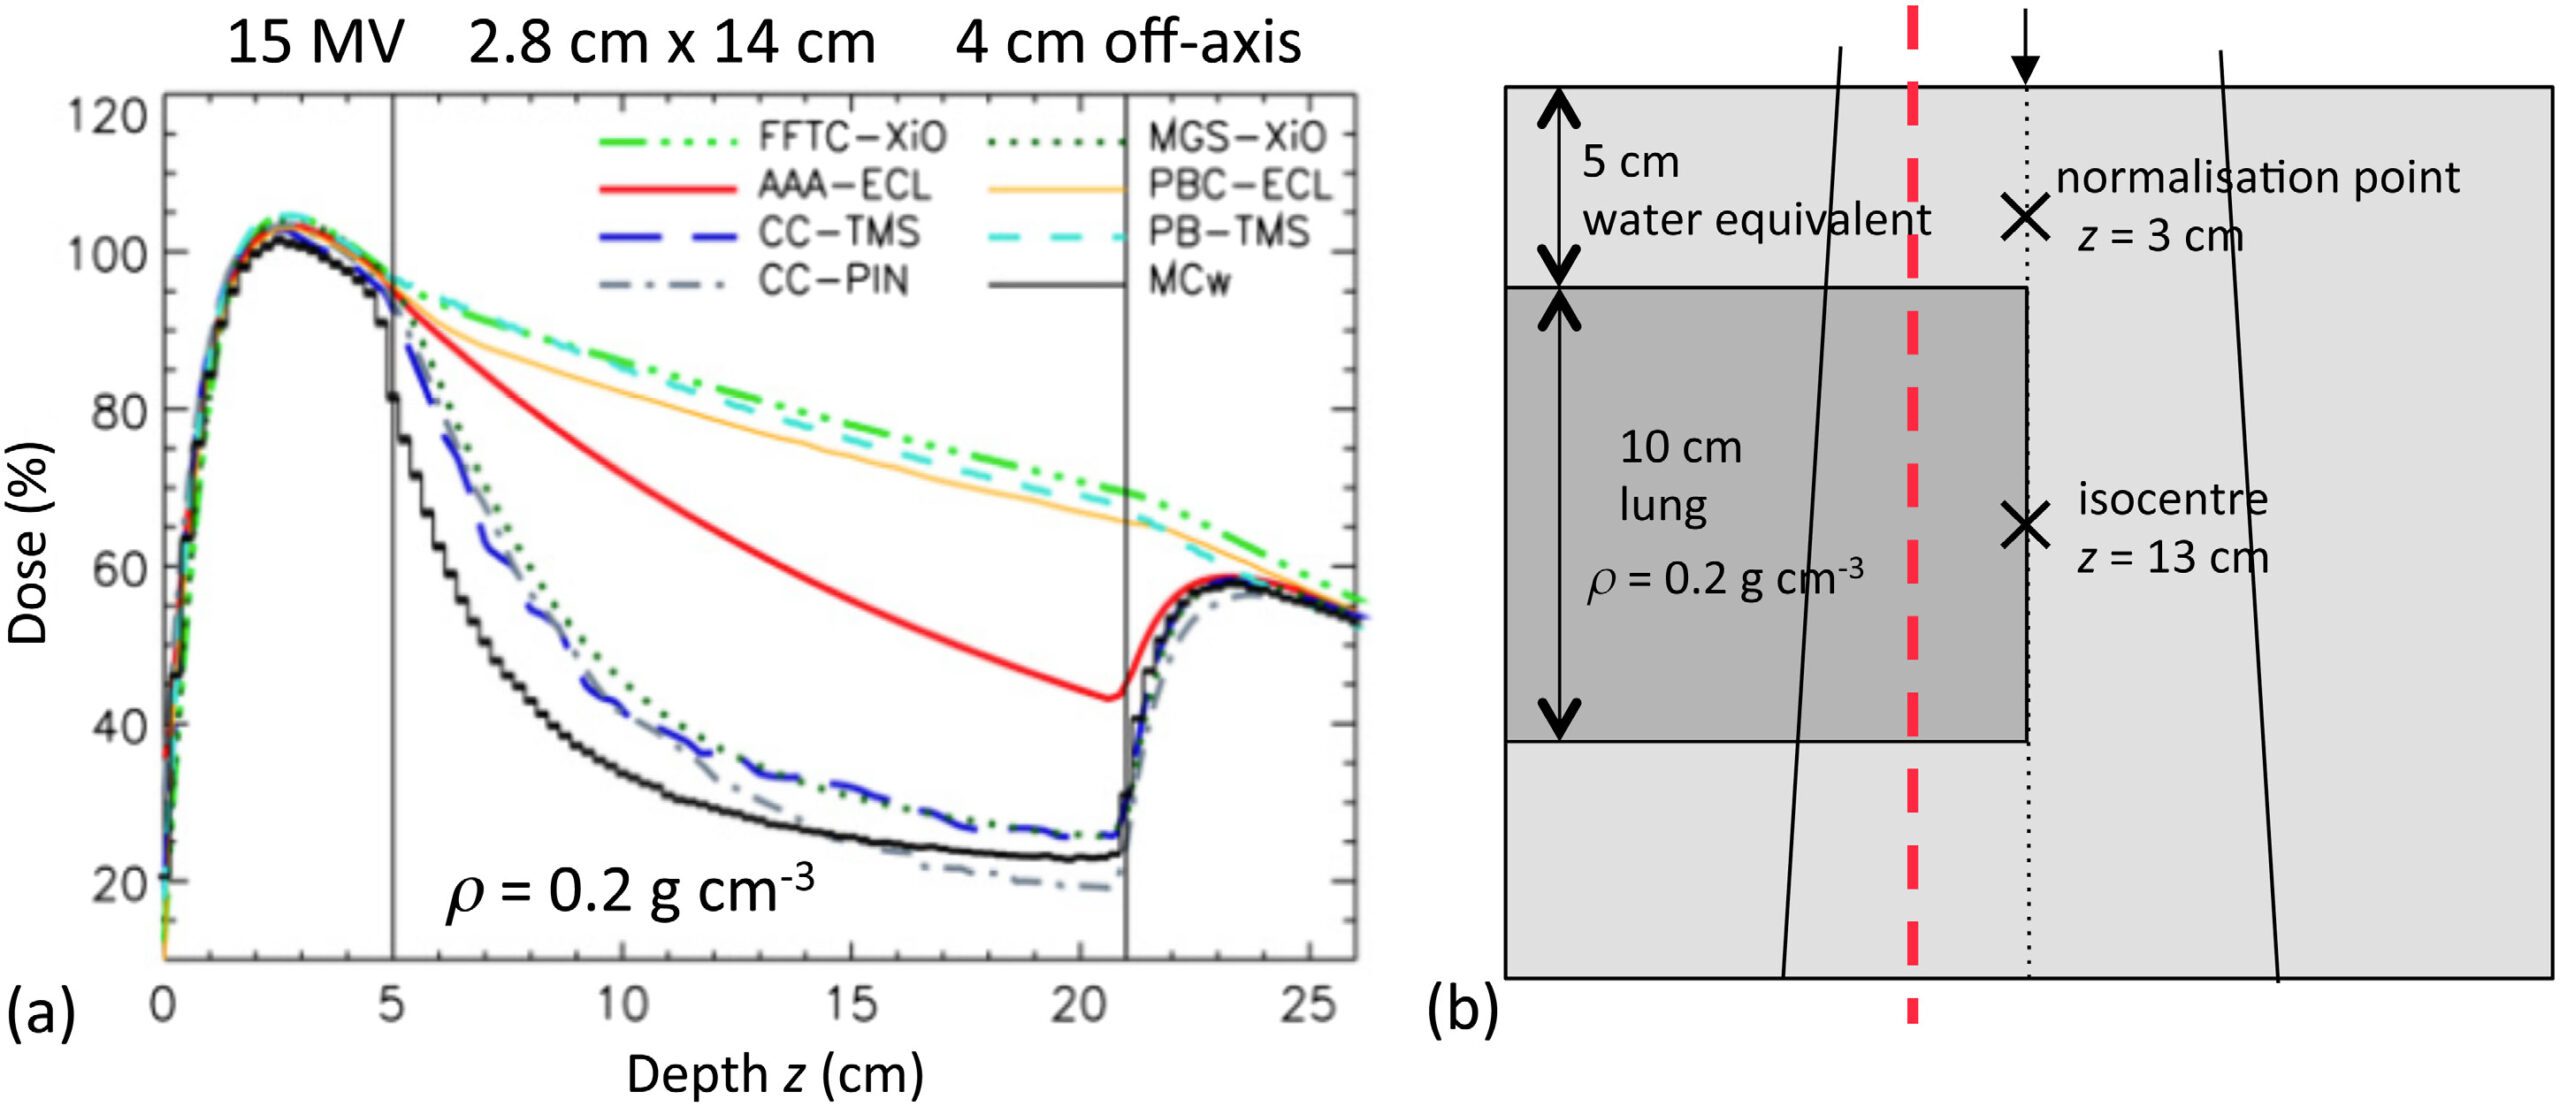

A diferença entre algoritmos se manifesta mais claramente em condições desafiadoras: campos pequenos, feixes de alta energia e heterogeneidades acentuadas — especialmente pulmão. A figura ao lado ilustra isso de forma dramática: para um feixe de 15 MV, campo 2,8×14 cm, 4 cm off-axis, atravessando 10 cm de pulmão (ρ = 0,2 g/cm³), as curvas de dose em profundidade divergem significativamente entre os algoritmos.

Monte Carlo ($MC_w$) serve como referência. O Collapsed Cone (CC-TMS, CC-PIN) acompanha razoavelmente bem, com desvios moderados na interface e dentro do pulmão. O AAA (AAA-ECL) segue de perto o CCC mas com desvios na interface tecido-pulmão. Já o Pencil Beam (PB-TMS, PBC-ECL) superestima a dose dentro do pulmão por uma margem clinicamente significativa e não consegue reproduzir a redução de dose lateral causada pela falta de equilíbrio eletrônico.